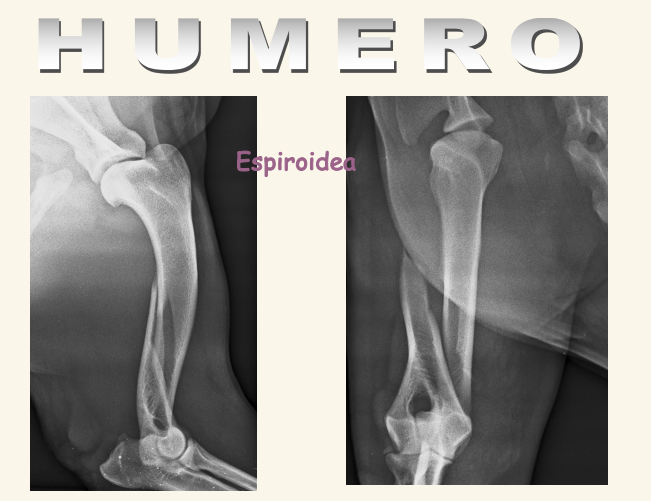

Humero:

Fracturas es lo mas comun, sobre todo en espiral. Pueden tener lesiones neuronales recuperables

Los sarcomas aparecen lejos del codo en extermidades anteriores y cerca de la rodilla en extermidades posteriores.

Las neoplasias sueln ser en la zona proximal del humero